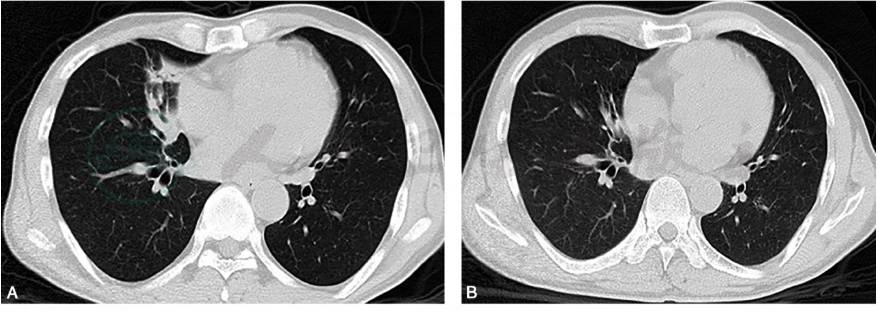

胸部CT(2013-12-18,图1):右肺中叶大片高密度影,伴支气管充气征;双肺多发结节影;纵隔淋巴结肿大。

图1 胸部CT:右肺中叶大片高密度影,伴支气管充气征;双肺多发结节影;纵隔淋巴结肿大

图3 胸部CT随访:青霉素治疗后3个月胸部CT(B)显示较治疗前(A)病灶已基本吸收消散